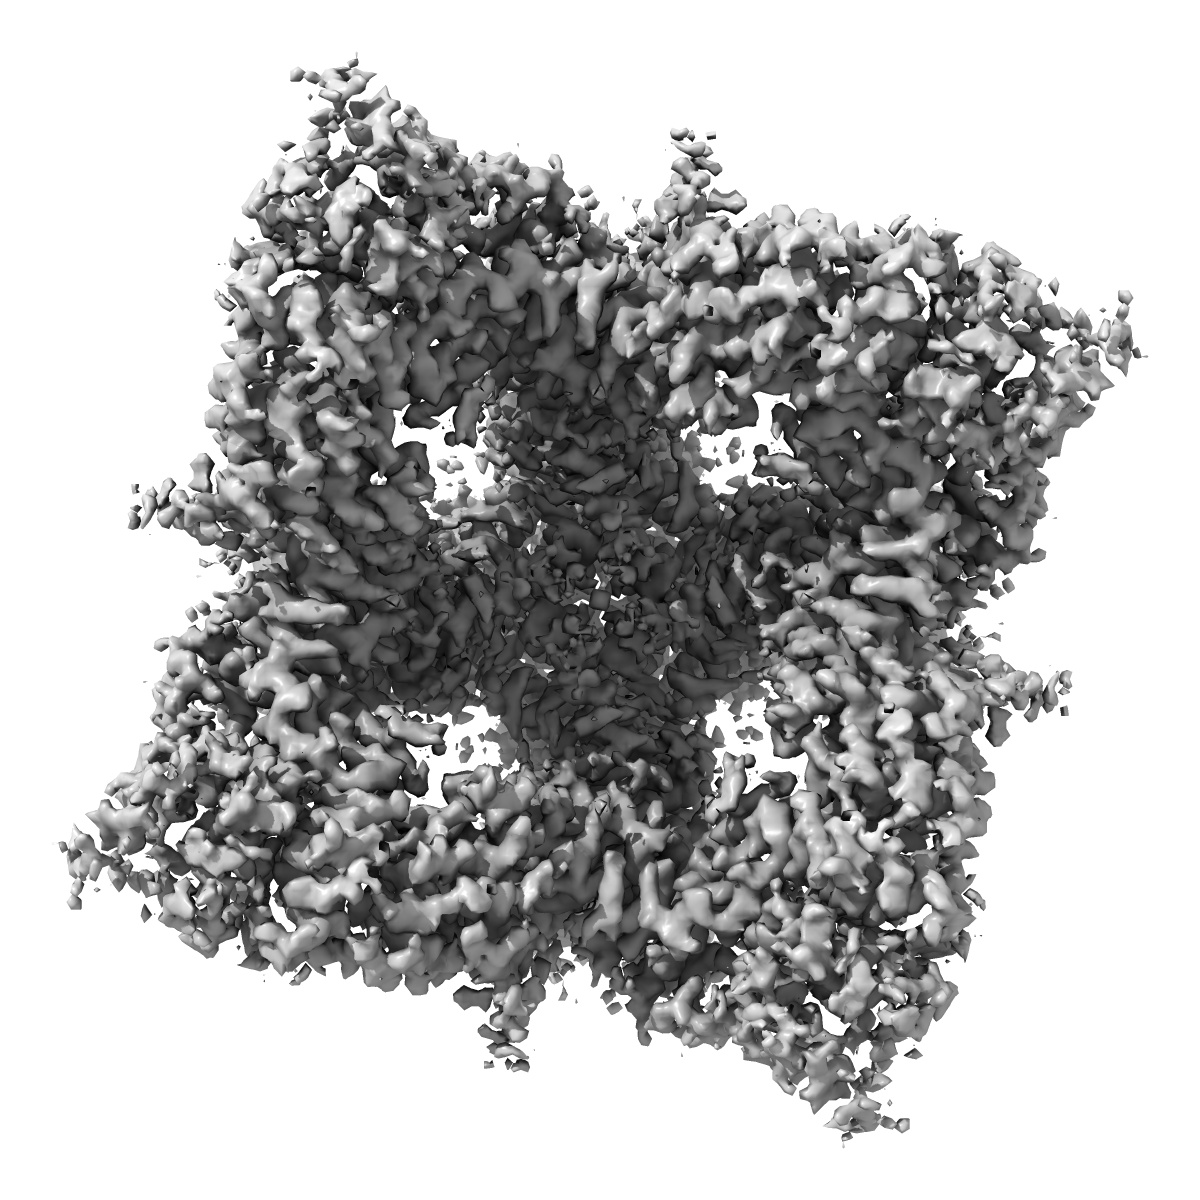

Cryo-EM structure of human TRPV6 in complex with inhibitor econazole

Structural mechanisms of TRPV6 inhibition by ruthenium red and econazole.

Neuberger A , Nadezhdin KD , Sobolevsky AI

(2021) Nat Commun , 12 , 6284 - 6284